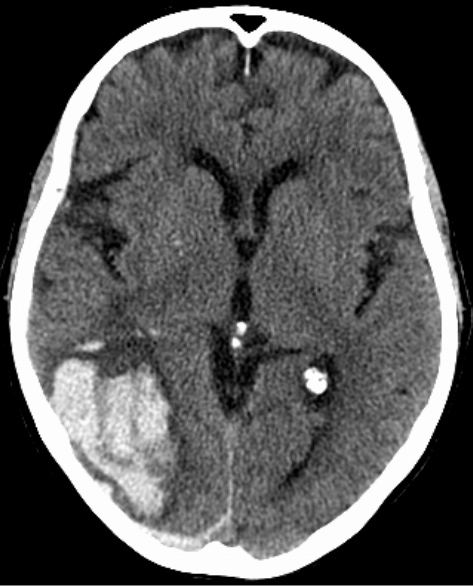

An 18-year-old man is brought to the emergency department following a generalized tonic-clonic seizure. He developed full body jerking at home this morning, which lasted approximately 1 minute. The episode occurred just before the patient was about to visit the clinic for evaluation of a worsening headache for the past 2 days. His parents say that he has also seemed clumsy over the same period, including tripping a few times yesterday. He has no history of seizures and was previously healthy except for seasonal allergies managed with over-the-counter medications. Temperature is 38.9 C (102 F), blood pressure is 130/80 mm Hg, and pulse is 92/min. The patient is awake but oriented only to person. Pupillary examination is unremarkable. The patient has bilateral hyperreflexia in the upper and lower extremities. MRI of the brain is shown below:

Which of the following is the most likely diagnosis for this patient?

A)Drug-induced encephalopathy

B)Herpes simplex virus encephalitis

C)Medulloblastoma

D)Reye syndrome

E)Subacute sclerosing panencephalitis

Which of the following is the most likely diagnosis for this patient?A)Drug-induced encephalopathy